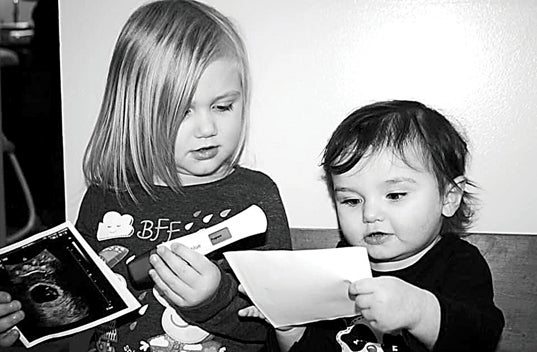

“I was sad, I felt like I was in denial,” she said. “I know it sounds weird, but I had two healthy baby girls before.”

While Presnell is in Ohio, her boyfriend and two daughters will be here in Tennessee due to childcare needs and him working. Without Presnell’s income to help support her family, she has set up a GoFundMe page to anyone who can help with expenses for her extended stay, and to help her family while she is gone. Additionally, she said at this time she doesn’t have many baby items.

Despite everything, Presnell and her family are excited to meet their baby girl, already brainstorming names. Presnell also has a message for other expectant moms who have this diagnosis.